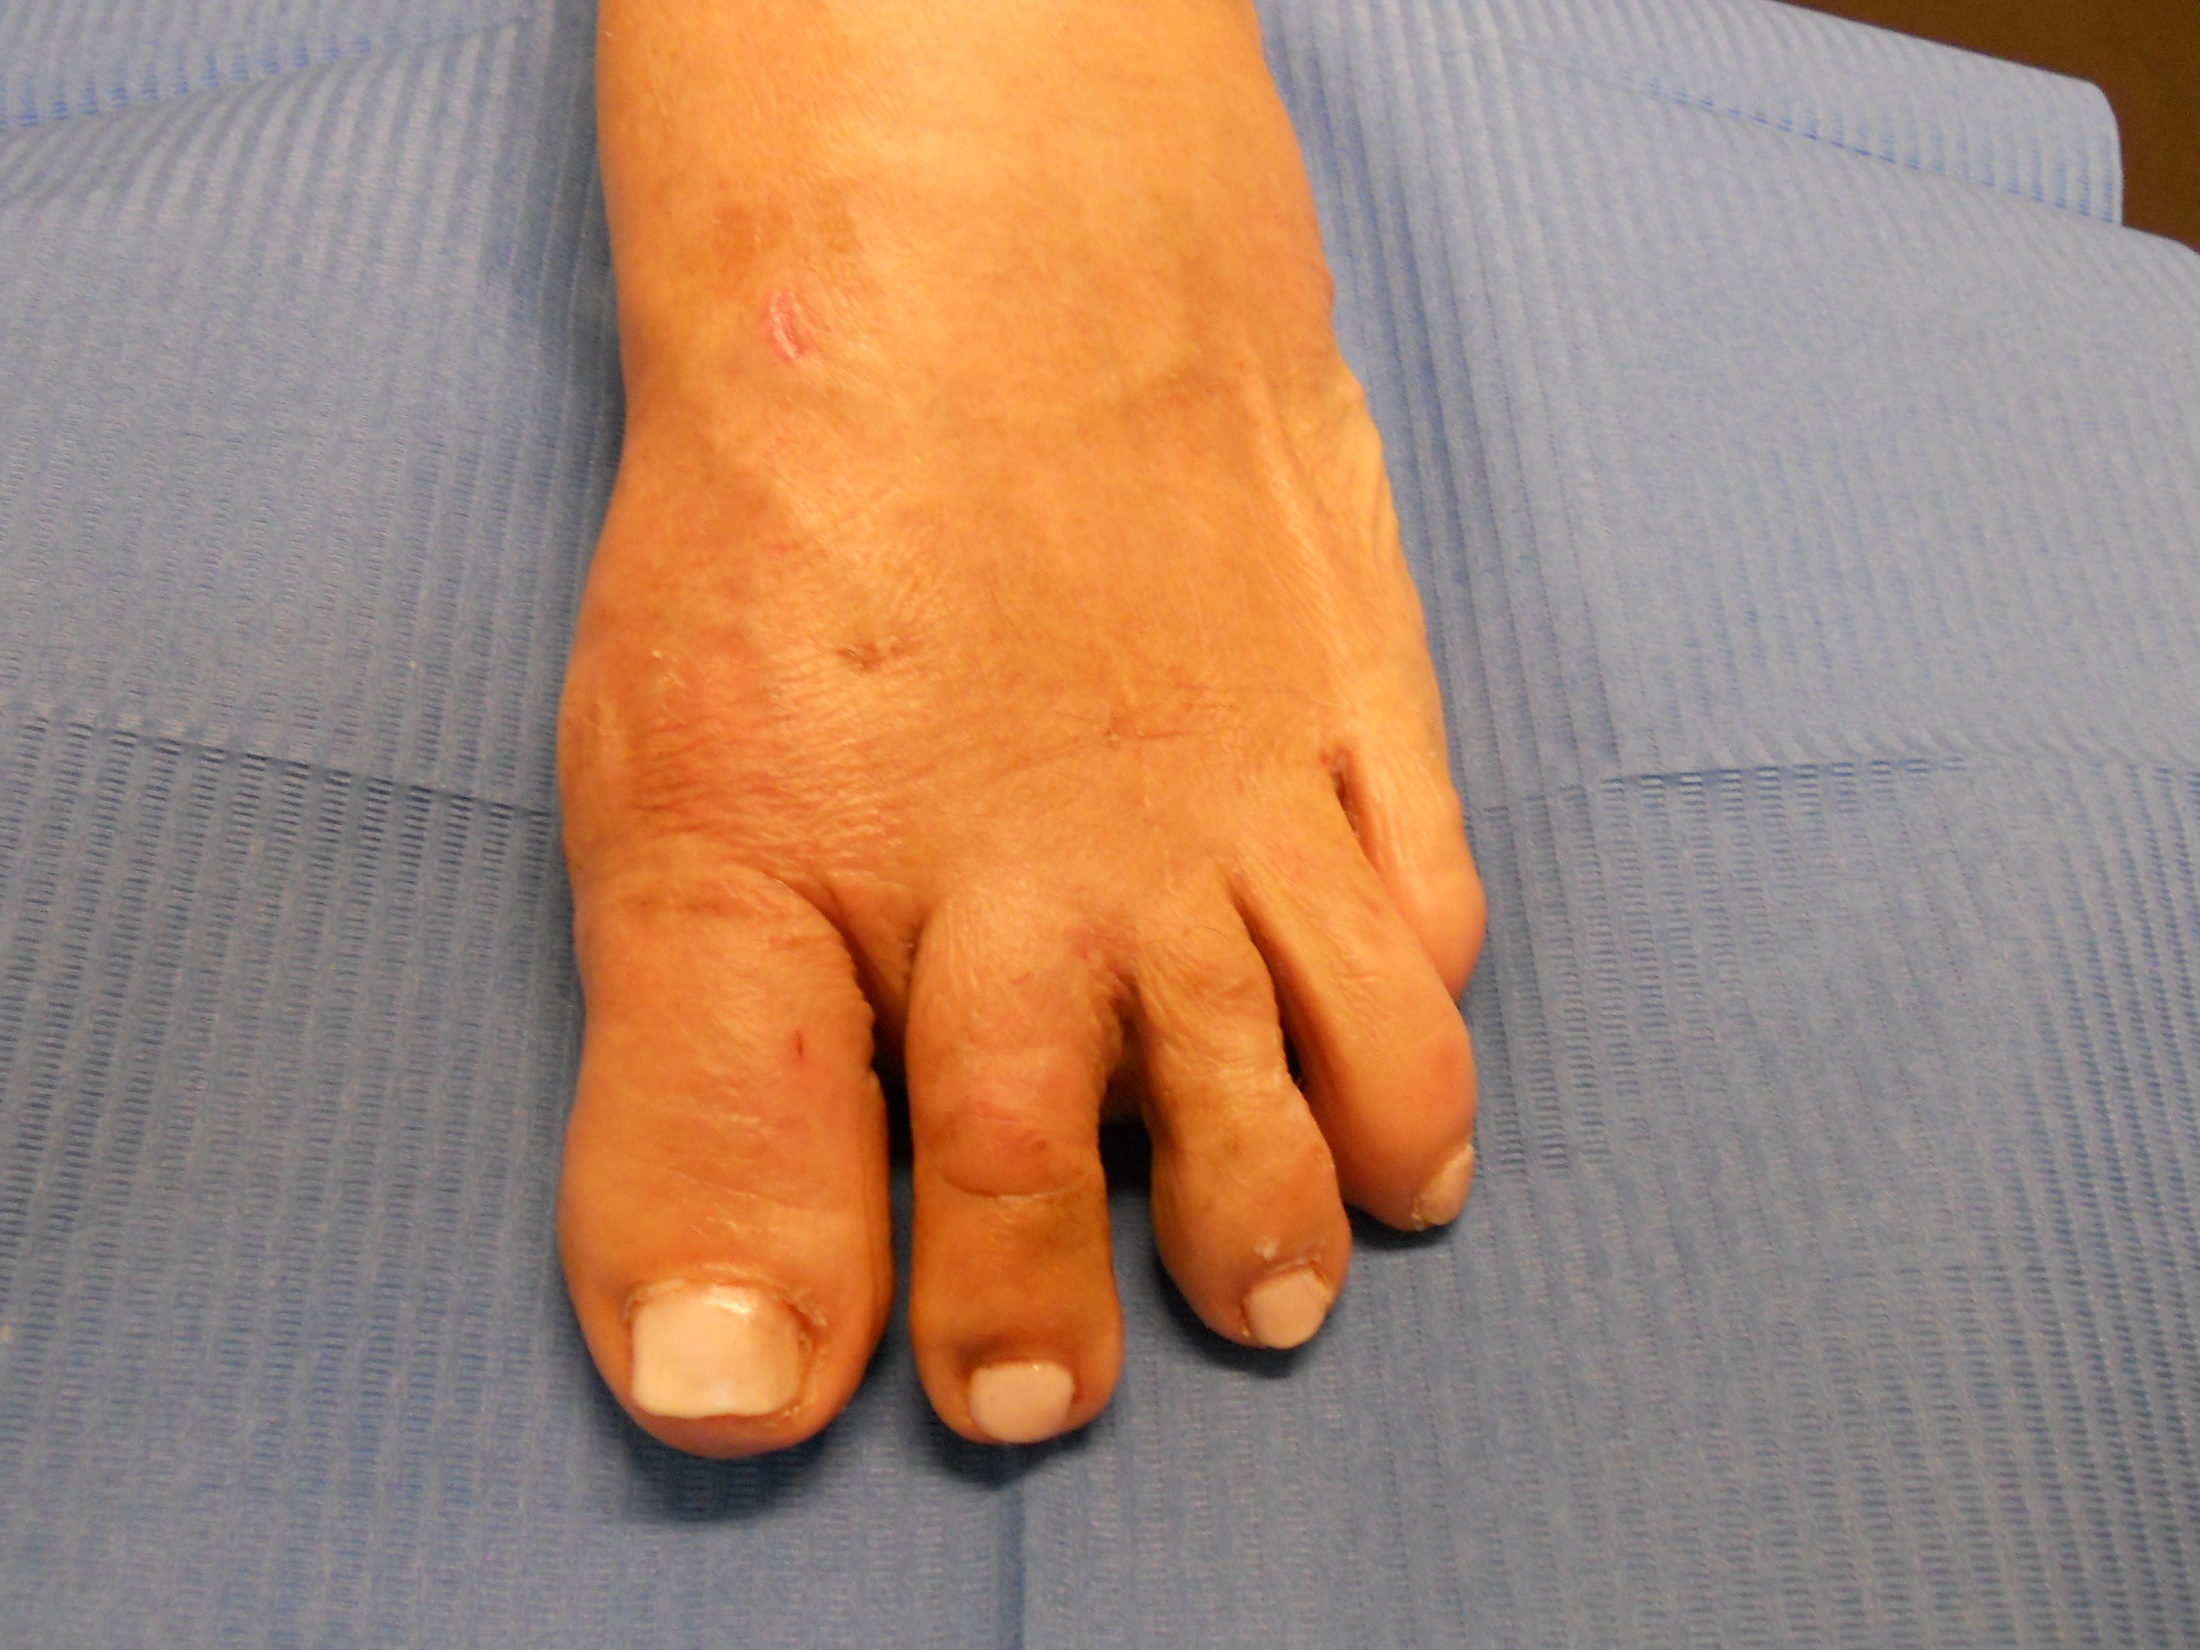

Hallux valgus (juanete) y dedos en garra

Hallux valgus (juanete) y dedos en garra: antes Hallux valgus (juanete) y dedos en garra: después